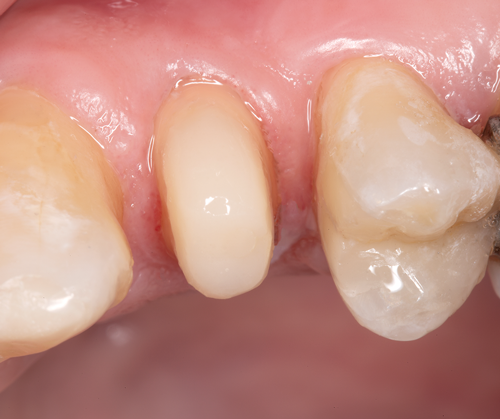

The completed post and core displayed an ideal ferrule dimension (Figure 23 and Figure 24). Radiographic review revealed an optimal integration at the adhesive interfaces (Figure 25). A laboratory-processed composite crown completed the optimal integration between the components of the post-retained system and provided structural integrity for intraradicular rehabilitation (Figure 26).

Fig 23. The completed post and core with an ideal ferrule dimension.

Figure 23

Fig 24. Occlusal view of the all-ceramic crown preparation with a full chamfer providing a 2 mm ferrule of sound tooth structure.

Figure 24